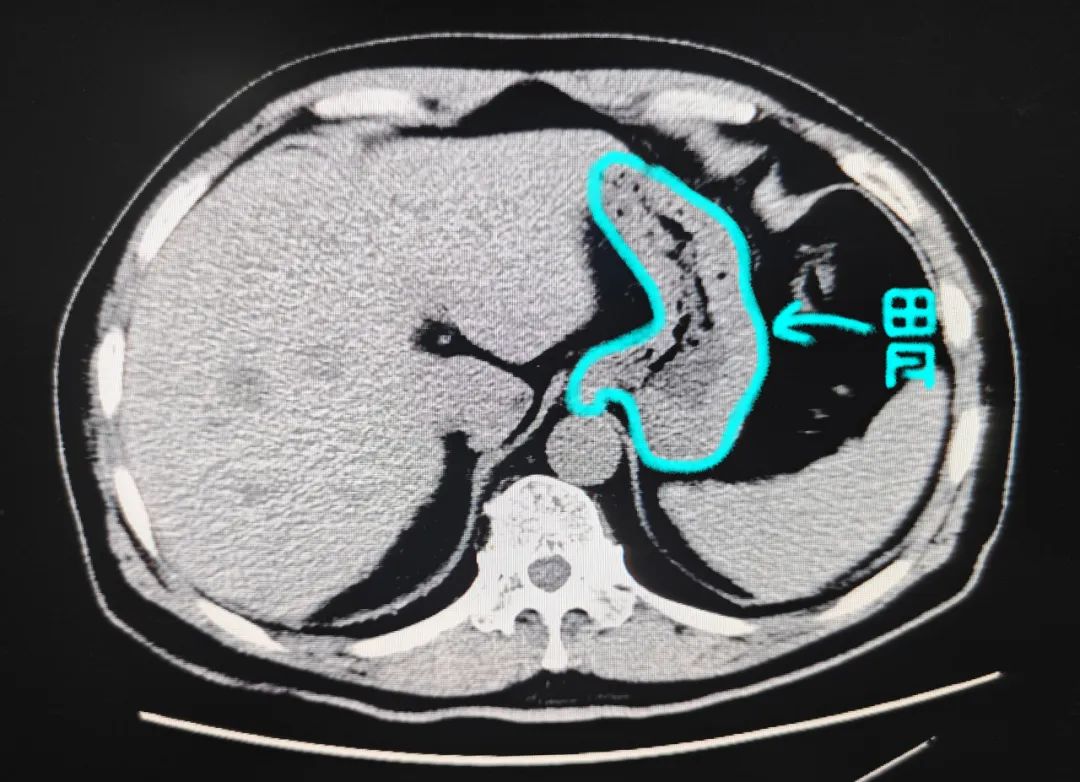

为充分饮水后已经做好准备的胃,里面装的都是水,胃壁被填充,成薄薄的一层,胃壁及胃壁外有异常病变,扫描图像可清楚显示。